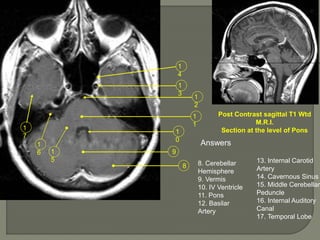

Post Contrast sagittal T1 Wtd

M.R.I.

Section at the level of Pons

Answers

8. Cerebellar

Hemisphere

9. Vermis

10. IV Ventricle

11. Pons

12. Basilar

Artery

13. Internal Carotid

14. Cavernous Sinus

15. Middle Cerebellar

Peduncle

16. Internal Auditory

Canal

17. Temporal Lobe